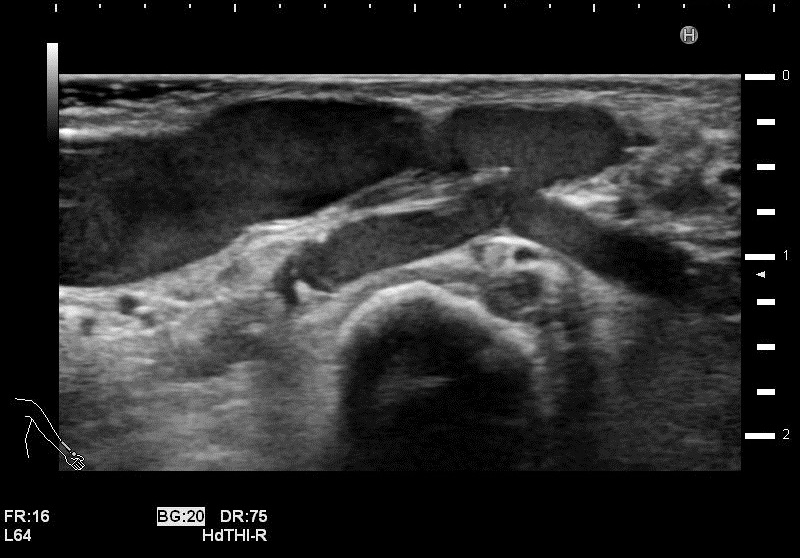

石灰化画像

吻合部画像

・吻合部の観察

吻合形態や、石灰化の有無、狭窄等を観察しています。